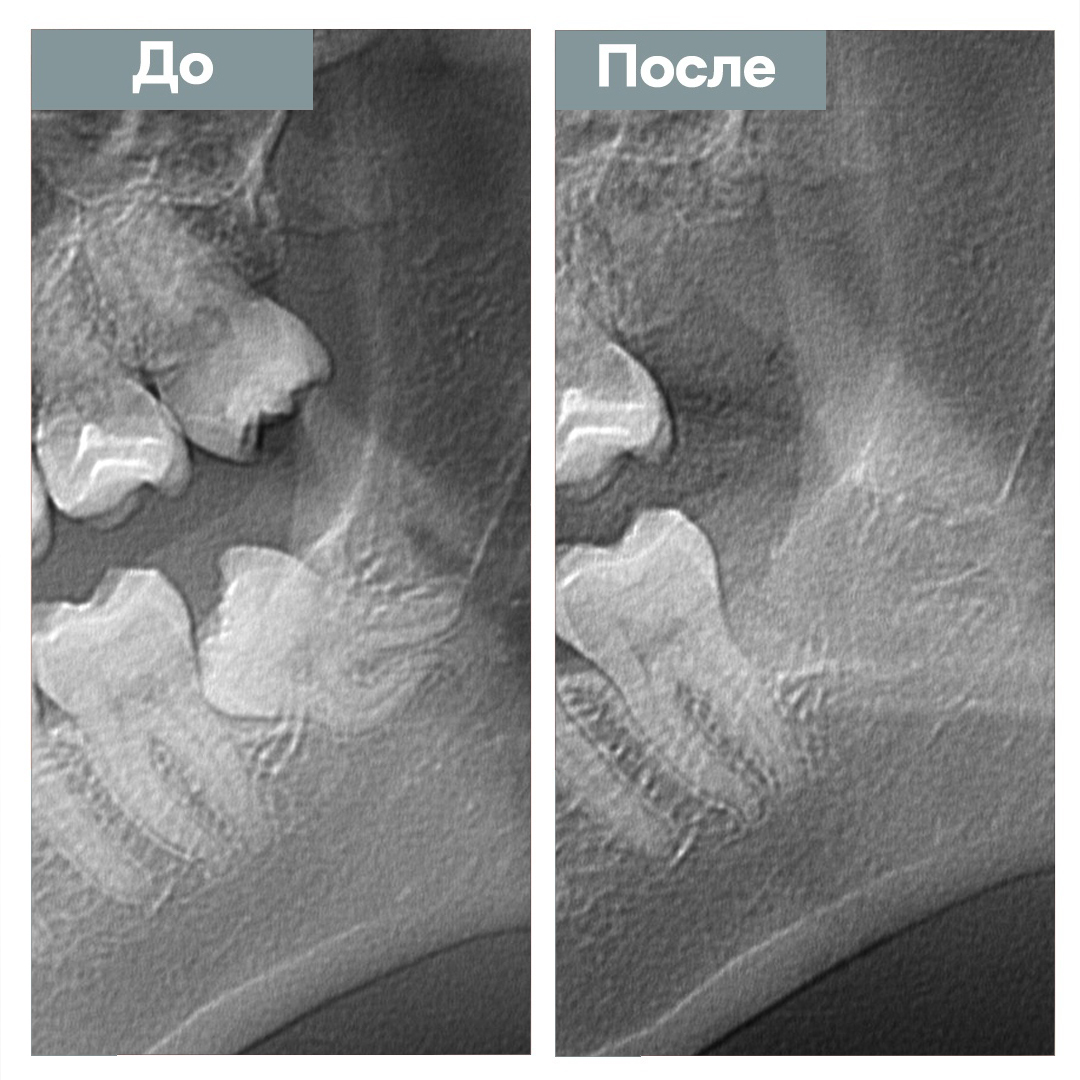

Удаление ретинированного зуба